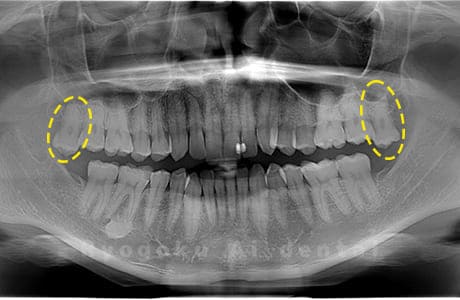

Case03

- 原因

- 上顎、下顎の親知らず

- 治療内容

- 上下4本の親知らずを抜歯したケースです。

<リスク・副作用>

手術後は痛み、腫れ、痺れなどの副作用が生じる場合があります。